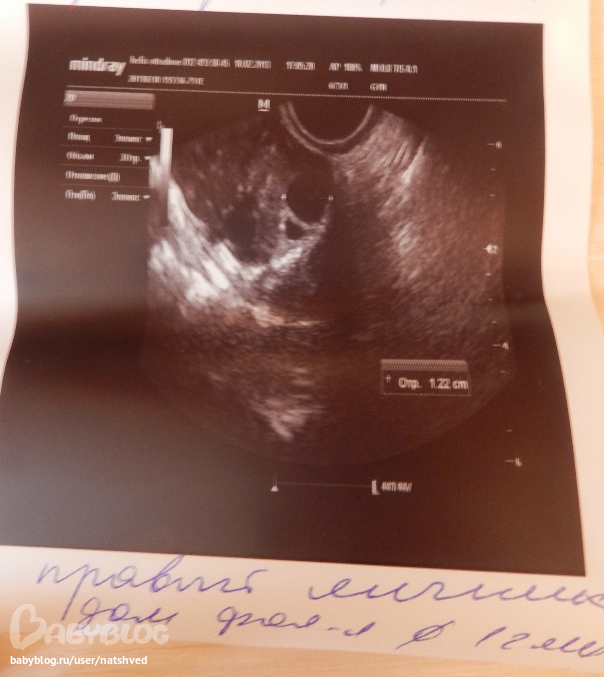

ПЯ ДФ 12мм